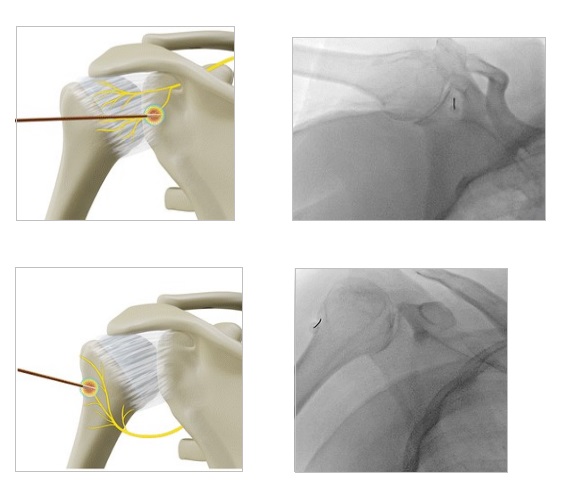

Τι είναι ο φαρμακευτικός αποκλεισμός και η εφαρμογή παλμικής ραδιοσυχνότητας στο υπερπλάτιο νεύρο

Η νευροπάθεια του υπερπλάτιου νεύρου μπορεί να αποτελέσει αιτία επίμονου, διαξιφιστικού πόνου σε ασθενείς με κατάγματα του ώμου και σε αθλητές, όπου μπορεί να παρατηρηθεί τραυματική έλξη του ώμου. Το υπερπλάτιο νεύρο είναι ευάλωτο στη συμπίεση. Το φαρμακευτικό block του νεύρου και ακολούθως η νευρόλυση με χρήση παλμικής ραδιοσυχνότητας, ανακουφίζουν από τον πόνο, χωρίς να χαθεί η κινητικότητα του άνω άκρου. Η διαδικασία νευρόλυσης αποτελεί μια ελάχιστα παρεμβατική πράξη, διενεργούμενη με υπερηχογραφική καθοδήγηση. Οι ασθενείς που έχουν ανταποκριθεί θετικά στον φαρμακευτικό νευρικό αποκλεισμό είναι ιδανικοί υποψήφιοι για την εφαρμογή της θεραπείας αυτής, η οποία θα προσφέρει μακρό σε διάρκεια αποτέλεσμα.

Τι είναι η απονεύρωση του ώμου με θερμοπηξία ή κρυοπηξία

Η οστεοαρθρίτιδα του ώμου αποτελεί αιτία σωματικής αναπηρίας και ψυχικής δυσφορίας. Η μη χειρουργική αντιμετώπιση συχνά δεν είναι σε θέση να αντιμετωπίσει πλήρως τον χρόνιο πόνο στις αρθρώσεις. Επιπλέον, ένας μεγάλος αριθμός ασθενών δεν είναι κατάλληλος για χειρουργική επέμβαση λόγω υποκείμενων σοβαρών προβλημάτων υγείας. Η κατάλυση με ραδιοσυχνότητες (RFA) ή κρυοκατάλυση (cryoablation) των αρθρικών αισθητήριων νευρικών ινών μπορεί να αναστείλει τη μετάδοση των αισθητικών σημάτων πόνου, προσφέροντας έτσι ουσιαστική ανακούφιση. Οι αρθρικοί αισθητικοί κλάδοι του υπερπλάτιου, του μασχαλιαίου και του πλάγιου θωρακικού νεύρου στοχεύονται κατά τη διάρκεια της μεθόδου, οι οποίοι αποτελούν την κύρια πηγή αισθητικής νεύρωσης του ώμου.

Η ελάχιστα επεμβατικές αυτές τεχνικές ενδείκνυνται επίσης, για συμπτωματική ανακούφιση σε ασθενείς που έχουν επίμονο πόνο μετά από χειρουργική επέμβαση αντικατάστασης της άρθρωσης.

Εφαρμόζονται με τοπική αναισθησία σε ξύπνιο ασθενή και κάτω από συνεχή ακτινοσκοπικό έλεγχο.